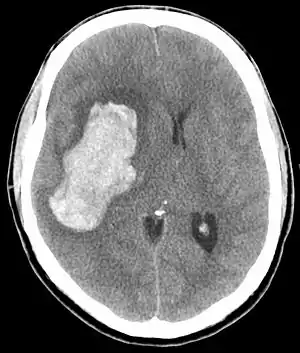

| CT scan depicting intracranial hemorrhage, a possible complication of hypertensive emergency. Patients with spontaneous intracranial hemorrhage present with newfound headache and neurologic deficits. | |

In the brain, hypertensive encephalopathy - characterized by hypertension, altered mental status, and swelling of the optic disc - is a manifestation of the dysfunction of cerebral autoregulation. Cerebral autoregulation is the ability of the blood vessels in the brain to maintain a constant blood flow. People with chronic hypertension can tolerate higher arterial pressure before their autoregulation system is disrupted. Hypertensives also have an increased cerebrovascular resistance which puts them at greater risk of developing cerebral ischemia if the blood flow decreases into a normotensive range. On the other hand, sudden or rapid rises in blood pressure may cause hyperperfusion and increased cerebral blood flow, causing increased intracranial pressure and cerebral edema, with increased risk of intracranial bleeding.[6]

Consequences of hypertensive emergency result after prolonged elevations in blood pressure and associated end-organ dysfunction. Acute end-organ damage may occur, affecting the neurological, cardiovascular, kidney, or other organ systems. Some examples of neurological damage include hypertensive encephalopathy, cerebral vascular accident/cerebral infarction, subarachnoid hemorrhage, and intracranial bleeding. Cardiovascular system damage can include myocardial ischemia/infarction, acute left ventricular dysfunction, acute pulmonary edema, and aortic dissection. Other end-organ damage can include acute kidney failure or insufficiency, retinopathy, eclampsia, lung cancer, brain cancer, leukemia and microangiopathic hemolytic anemia.